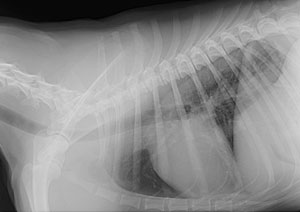

Radiology - the use of high quality digital radiographs aids in the diagnosis and treament of many disorders, and also allows a quicker consultation with specialists when needed.